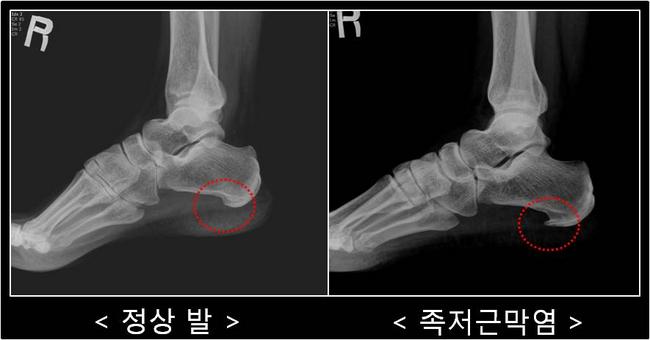

이미지=구글

겨울철 기온이 떨어지면 발뒤꿈치 통증을 호소하는 이들이 크게 늘어난다. 특히 아침에 일어나 첫 발을 디딜 때 “발바닥이 찢어지는 듯하다”고 표현하는 경우가 많은데, 이는 족저근막염 초기 증상으로 잘 알려져 있다. 계단을 내려가거나 오랜 시간 서 있을 때 통증이 갑자기 심해지는 것도 특징이다. 전문가들은 이를 방치할 경우 만성 통증으로 이어질 가능성이 높아 조기 관리가 필요하다고 강조한다.

족저근막은 발뒤꿈치뼈에서 발가락 기저부까지 이어지는 강한 섬유 조직으로, 발의 아치를 유지하고 보행 시 충격을 흡수하는 핵심 구조다. 장시간 서 있거나 과도하게 걷는 생활이 반복되면 이 조직에 미세 손상이 쌓여 염증이 발생한다. 최근에는 스마트폰과 PC 사용 증가로 종아리와 아킬레스를 이루는 근육·건이 짧아지면서 발의 하중 분산이 어려워지고, 이로 인해 증상이 악화되는 사례도 보고되고 있다.